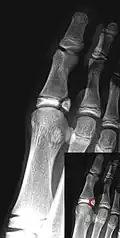

Salter–Harris III fracture of big toe proximal phalanx. -